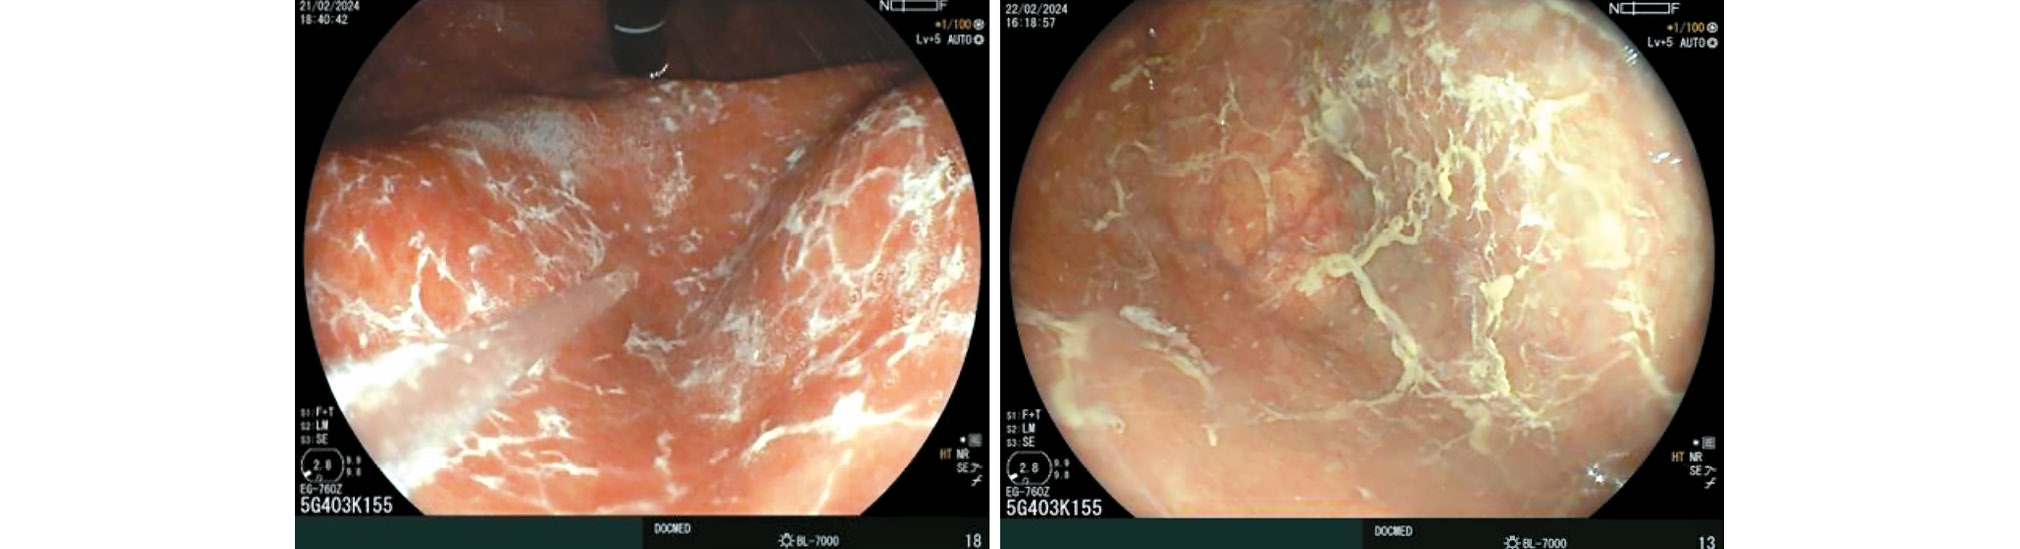

Esophagogastroduodenoscopy with biopsy is the primary method for diagnosing autoimmune gastritis. Reports from the late 19th and early 20th centuries described gastric body atrophy in patients with pernicious anemia. In 85% of these cases, atrophic changes were more pronounced in the gastric body (Fig. 1) [40].

Fig. 1. Diffuse atrophy of the gastric body mucosa when examined in inversion (a) and direct projection (b). © Eco-Vector, 2025.